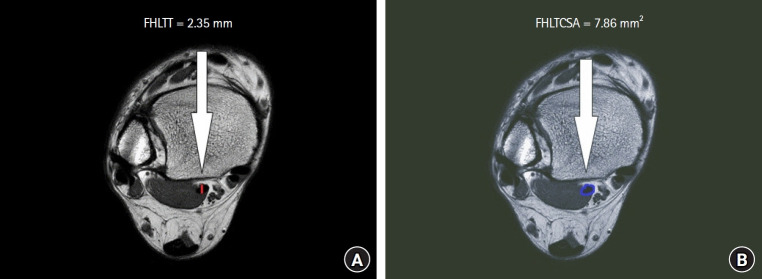

Methods: 26 participants in the Control group (Group 1) and 26 in the FHLTS group (Group 2) underwent magnetic resonance imaging. The FHLTCSA was calculated for the ligament based on the images showing the maximum hypertrophic changes. The FHLTT was measured based on the images showing the FHLT with the maximum thickness.

Results: The mean FHLTCSA was 7.86 ± 1.88 mm2 and 13.11 ± 2.31 mm2 in Groups 1 and 2, respectively. The average FHLTT was 2.35 ± 0.55 mm and 2.91 ± 0.37 mm in Groups 1 and 2, respectively. The FHLTCSA (P < 0.001) and FHLTT (P < 0.001) in Group 2 were significantly greater than those in Group 1. Receiver operating characteristic curve analysis revealed that the optimal cutoff value for the FHLTCSA was 10.37 mm2, with a sensitivity of 92.3%, a specificity of 92.3%, and an area under the curve (AUC) of 0.97. The optimal cutoff value for the FHLTT was 2.71 mm, with a sensitivity of 76.9%, a specificity of 76.9%, and an AUC of 0.84.